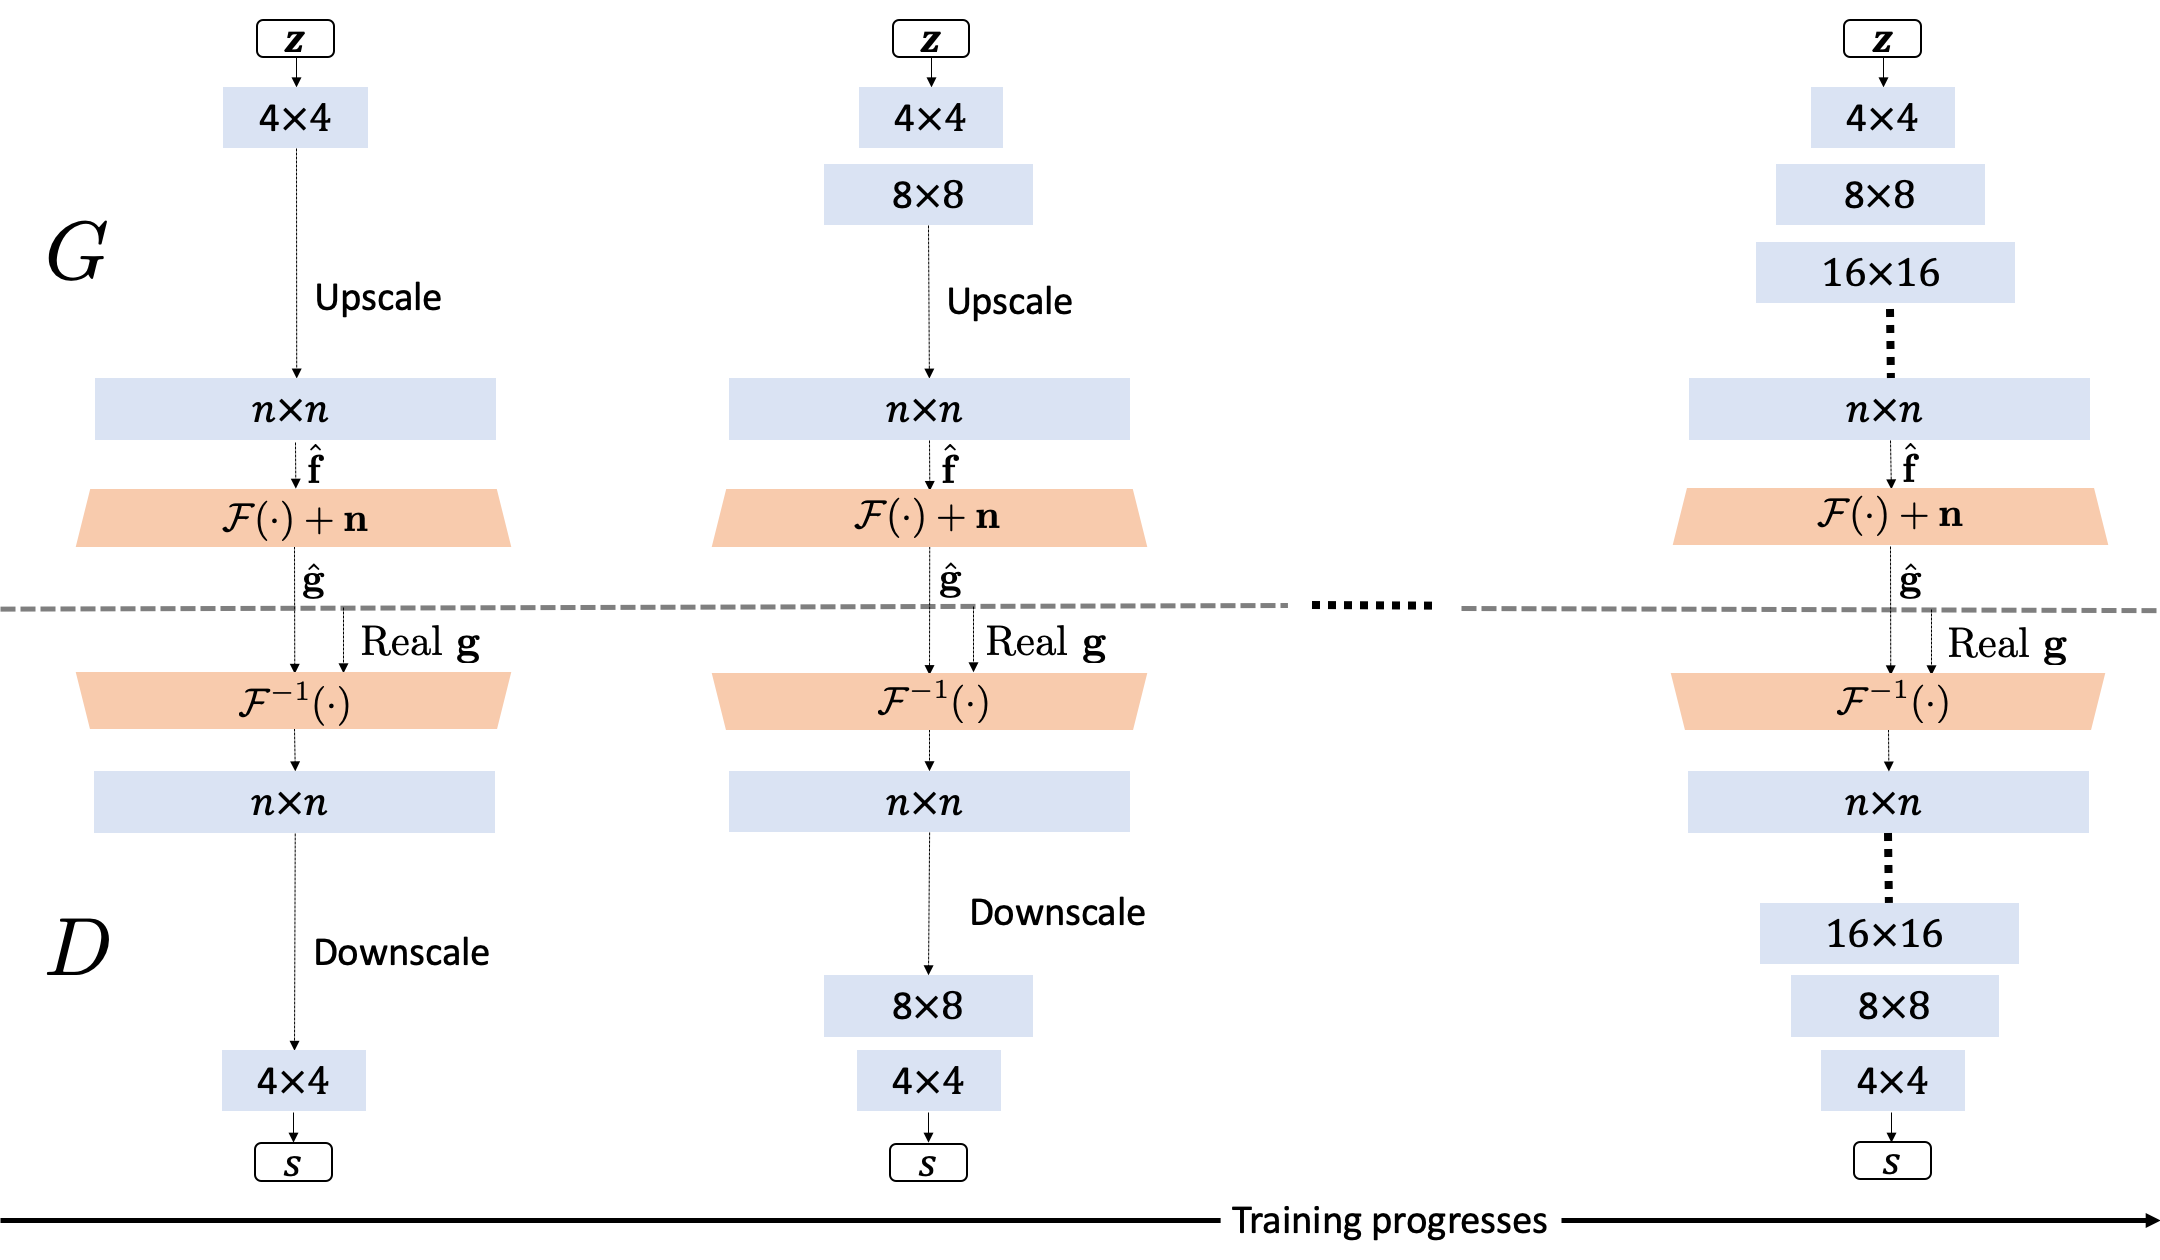

A recently developed GAN training methodology—Progressive Growing of GANs (ProGANs)—holds great promise to stabilize the training of GANs and has been successfully employed to generate high-quality synthetic images with high resolutions[10]. Unlike the conventional training of GANs, in which all scales of the image distribution are learned simultaneously, the training of ProGANs starts with low-resolution images. Subsequently, network layers are added progressively to the generator and discriminator in synchrony to increase the image resolution for learning finer scale details of the image distribution. Here, the generator and the discriminator have mirrored architectures. It has been shown that GAN training stability and the quality of the produced synthetic images can be improved significantly by use of this training strategy[10]. However, because medical imaging systems record noisy and indirect measurements of object properties, ProGANs cannot be immediately applied to establish stochastic models of objects to-be-imaged.

Progressive Growing of GANs (ProGANs) were developed to stabilize the training of GANs[10]. Unlike the conventional GANs, in which the generator and the discriminator are trained to learn all scales of image distribution by use of full resolution images through the whole training process, the training of ProGANs start with training the first few layers of the generator and discriminator on low-resolution images that are down-scaled from the original images. Higher-resolution images are subsequently employed and more layers of the generator and discriminator are progressively included in the training to learn finer scale details of the image distribution. It has been shown that the ProGAN training strategy results in significantly improved training stability and produces synthetic images with the state-of-the-art image quality[10]. However, like other GANs, ProGANs cannot be immediately applied to learn SOMs from noisy and/or indirect imaging measurements.

3 Progressive Growing of Ambient-GANs

In this work, we propose a novel training strategy named Progressive Growing of AmbientGANs (ProAGANs) to stably train the AmbientGANs for establishing SOMs from noisy and indirect imaging measurements. A MR imaging system that fully samples k-space data was considered: , where denotes a 2D discrete Fourier transform (DFT). The generator in the proposed ProAGAN was trained to synthesize images that depict object properties in the to-be-imaged distribution. However, because the MR imaging system records noisy k-space measurement data, the discriminator cannot be applied directly to distinguish between real and synthetic object images. In our proposed architecture of ProAGAN, a 2D inverse discrete Fourier transform (IDFT) is included in the training of ProAGAN to reconstruct object images from k-space measurements, and the discriminator is trained to distinguish between real and synthetic reconstructed images. The goal is to learn the distribution of images that depict to-be-imaged object properties by progressively training a generator by competing against a discriminator that distinguishes between real and synthetic reconstructed images. This training process is illustrated in Fig. 1.

The proposed ProAGAN was implemented in Tensorflow[13] by modifying the ProGAN codes to apply the architecture illustrated in Fig. 1. The codes for the ProGAN can be found at https://github.com/tkarras/progressive_growing_of_gans. The ProAGAN was trained by use of 4 NVIDIA Tesla V100 GPUs. The Adam algorithm [14], which is a stochastic gradient algorithm, was employed to train ProAGANs.